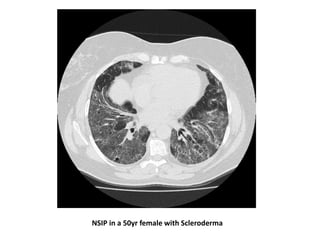

NSIP in a 50yr female with Scleroderma

• The majority of patients with SSc-ILD have NSIP-

pattern injury. Less commonly a UIP pattern is

observed, and other histopathological patterns

(e.g., OP or DAD) are very rare

• The most common radiographic findings for these

patients are ground glass opacities and fibrosis

• Patients with lung involvement greater than 20%

on HRCT and a FVC <70% of predicted were most

likely to progress without therapy